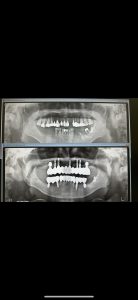

インプラント顎骨形態、頭に叩き込む💦

見ていると、脳みそに染み込む🤪

すっ〰️と身体が反応するようになる!